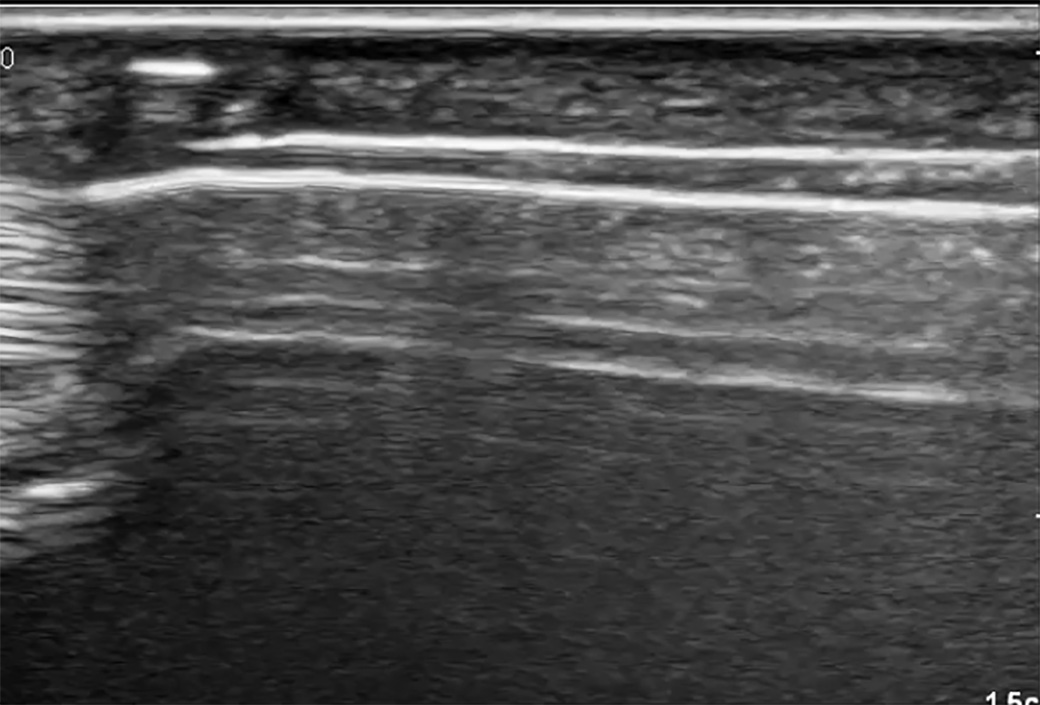

Designed for sonographically guided A1 annular ligament release, the guide is used with the included 2.3 mm hook knife, and the release is carried out via a small incision while the operation is carried out quasi percutaneously using sonographic control